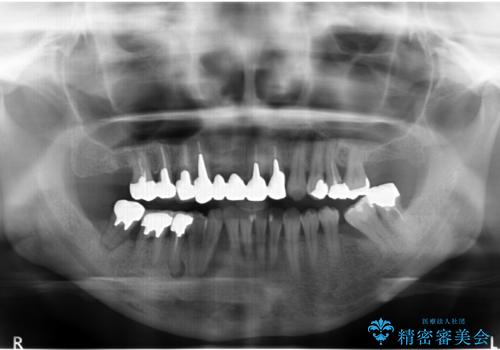

- 全体的な虫歯治療、根管治療、および歯周病治療を行いました。

歯周病治療につきましては歯周ポケット除去のために歯周外科処置(APF)を行っています。

左下6の欠損については左下7はワイヤー部分矯正でアップライトを行い、補綴スペースを確保しています。

右下犬歯は歯周病の進行が重度のため、やむなく抜歯をし、骨増生後にインプラント埋入を行っています。

根管治療は横浜桜木町歯科 大元先生が担当しました。

右下7の根管治療および再植は銀座院 林先生が担当しています。(抜歯は希望されなかったため、再植を行い、現在経過観察中です。)